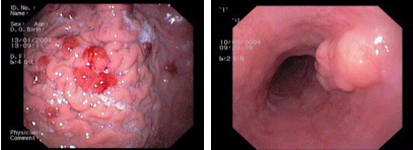

Endoscopic images:

imagen4

Fundic gland hyperplasia in the stomach, a common benign condition